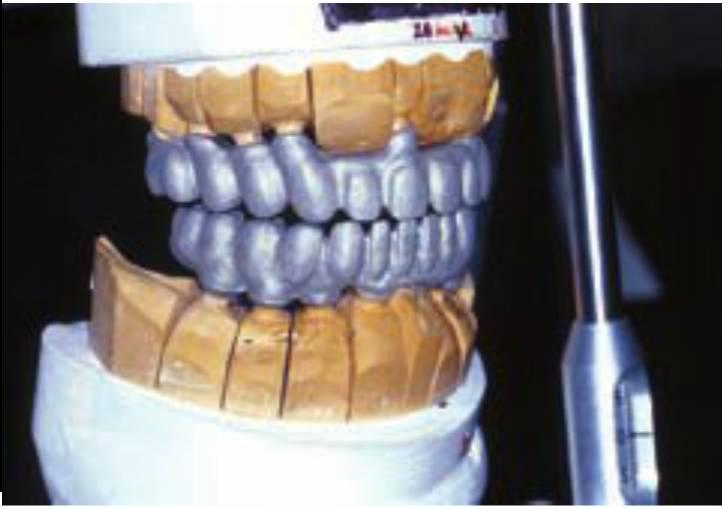

Las técnicas de mejor afinación para las restauraciones fijas tradicionales permitieron a Dabrowsky manufacturar y monitorizar múltiples casos edéntulos totales, prótesis cemento-retenidas con un amplio EAO llegadas a múltiples centros en Estados Unidos. Cada vez fue más difícil controlar los poros de la superficie de las subestructuras metálicas después de fundirlas, ya que sus distintas partes se enfriaron en diferentes rangos. Más aún, cuando el material fundido se reinserta en el horno para cocer la porcelana, se mantiene el calor dentro del material fundido en diferentes rangos, por lo que la porcelana se enfría en las distintas regiones con rangos diversos. Si no se controla adecuadamente, estos dos factores aumentan el riesgo de fractura de la porcelana al cargarse. Debido a un excesivo EAO, el peso considerable de la prótesis (casi 85 g de aleación) puede afectar a los puntos de apoyo del complejo maxilar, ya que las restauraciones no se mantienen en su sitio sin el uso de un adhesivo. Se deben usar metales nobles para controlar la expansión de calor de la aleación o la corrosión; por ello, se ha aumentado dramáticamente el coste de estas restauraciones implantológicas. Se han propuesto métodos para crear estructuras huecas para aliviar estos problemas, incluyendo el uso de cubetas individuales para conseguir un ajuste pasivo, que doblarán o triplicarán los costes de trabajo.